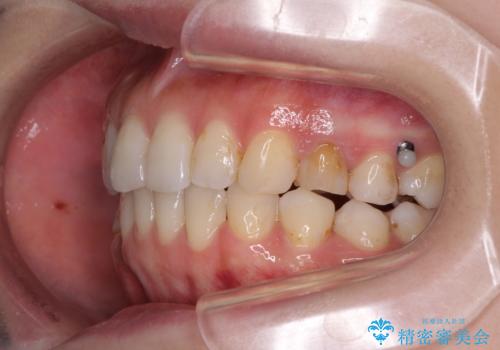

- 失活により変色した歯と不揃いな口元を気にして来院された患者様です。

口元をインビザラインにより歯列を整え、その後に失活している奥歯をオールセラミッククラウンにて補綴治療することとしました。